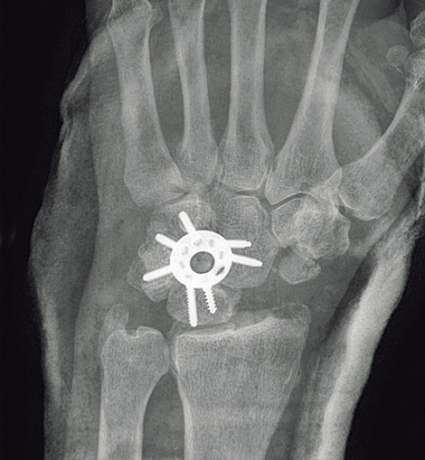

Vid SLAC-handled med artrosutveckling är någon typ av smärtlindrande salvage-operation enda möjligheten. Vid SLAC grad I, där artrosen är lokaliserad till enbart styloiden, kan en begränsad åtgärd, såsom radial styloidektomi ge ett bra resultat i några år. När artrosen spridit sig till hela scaphoideum-fasetten är de vanligaste metoderna s k four-corner-artrodes (steloperation mellan lunatum, capitatum, hamatum och triquetrum samt avlägsnande av scaphoideum) eller s k proximal row carpectomy (PRC). I ett 5–10-årsperspektiv ger dessa operationer likartat resultat, med ca 30–40 graders bibehållen flexion och extension samt ca 75 procents bevarad greppstyrka jämfört med den friska handleden [4].

När midkarpal artros förligger är enda operationsalternativet four-corner-artrodes. I sent skede med panartros tvingas man ofta utföra total handledsartrodes, och i speciella fall kan handledsprotes komma i fråga.